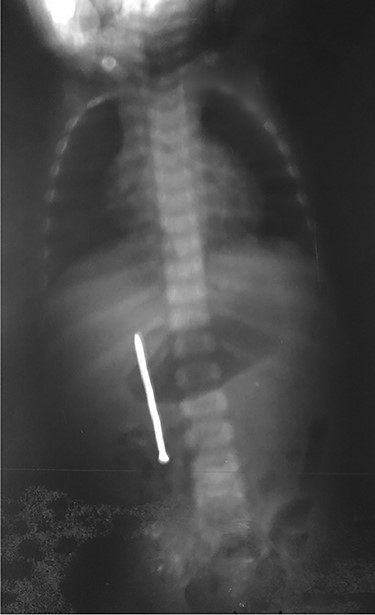

Urgent laparotomy exploration was planned. Intraoperatively, the nail was impacted and palpated through ascending colon wall. The nail was extracted through a minim colic incision centered on its head (Fig. 3), measuring ~6 cm. The ascending colon was mobilized, showing a second part of duodenum anterior wall (Fig. 4) and ascending colon posterior wall perforations (Fig. 5). There was neither peritonitis nor intraperitoneal free fluid. No spillage was noticed in the peritoneal cavity. Intraoperative diagnosis of duodenocolic fistula by nail ingestion was made. All perforations were repaired primarily (by multiple simple interrupted sutures) and drain was placed near repairs (Fig. 6). The follow-up was uneventful. The child was discharged on day 8.

In our case, according to the nail’s position on abdominal radiography, perforations were probably due to duodenal wall extension and progressive erosion of the nail’s head through the duodenal wall [3–5]. Our patient did not present signs of peritonitis neither free peritoneal air (pneumoperitoneum) because the site of duodenal perforation was covered by adjacent loops of ascending colon. This avoids the passage of intraluminal air into the peritoneal cavity.

Plain radiography plays the main role both in the diagnosis and the choice of operative interventional moment—either by pinpointing the radio-opaque image, or by showing certain FB characteristics, or by noting images suggesting complications (absent in our case), or even by projecting the FB in the same place over a period of time, an aspect inductive of fistula. In our case, right-edge superposition of the FB image upon the lumbar spine is characteristic of FB positioning in the second part of duodenum [5, 6]. Its persistence in the same place (the second part of the duodenum as in our case) suggests the presence of a duodenal fistula or perforation, which requires surgical intervention [7].